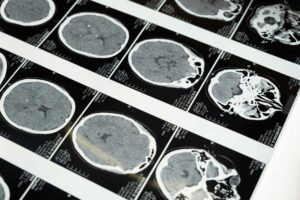

First off, MRIs—they’re not miracle machines. They show some stuff, but they’re not all-seeing. You could be experiencing crippling pain, yet the MRI could look like a snapshot of a calm lake. Here’s why:

- Small injuries evade the spotlight: Micro-tears in muscles or subtle nerve damage? MRIs just might miss them. Like trying to spot a single thread in a tattered cloth—small stuff hides.

- Invisible damage, real agony: MRI excels at spotting big-ticket injuries like disc herniations but fails to capture the quieter culprits—whiplash, soft tissue strain, or nerve damage. Think of it as looking through a narrow keyhole when the room’s much larger.